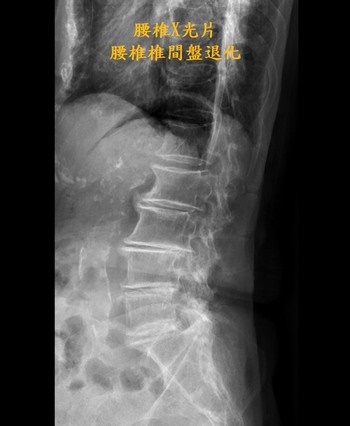

一旁陪伴的兒子林先生表示,其實母親三年前因腰椎椎管狹窄壓迫到神經導致她腰痛難受,母親痛到吃不下,走不了,坐著痛、站著也痛,不僅吃止痛藥沒有用,嚴重時只能躺在床上至少有二十二小時,還瘦了七公斤,看過多位醫師都說只能透過開刀來改善,但母親不想手術,因為擔心開刀的手術風險以及可能復發等後遺症,為了母親的生活品質,他尋覓合適的治療方式,還好當時透過網路找到有做疼痛介入性治療的王柏凱主任,就帶著母親來求醫。

王柏凱主任說,當時詹女士的第五腰椎跟薦椎間中間的椎間盤嚴重退化,因神經孔過小壓迫到神經,導致左邊的坐骨神經痛,當時做了硬脊膜外注射、增生療法等治療,疼痛明顯改善,但是效果只能維持約三個月;詹女士因為有膝蓋的骨內注射療法大大改善疼痛的經驗,與病人討論後,在今年七月的腰椎治療,也加入了骨內注射治療,如今詹女士已五個月沒感受到腰痛了。